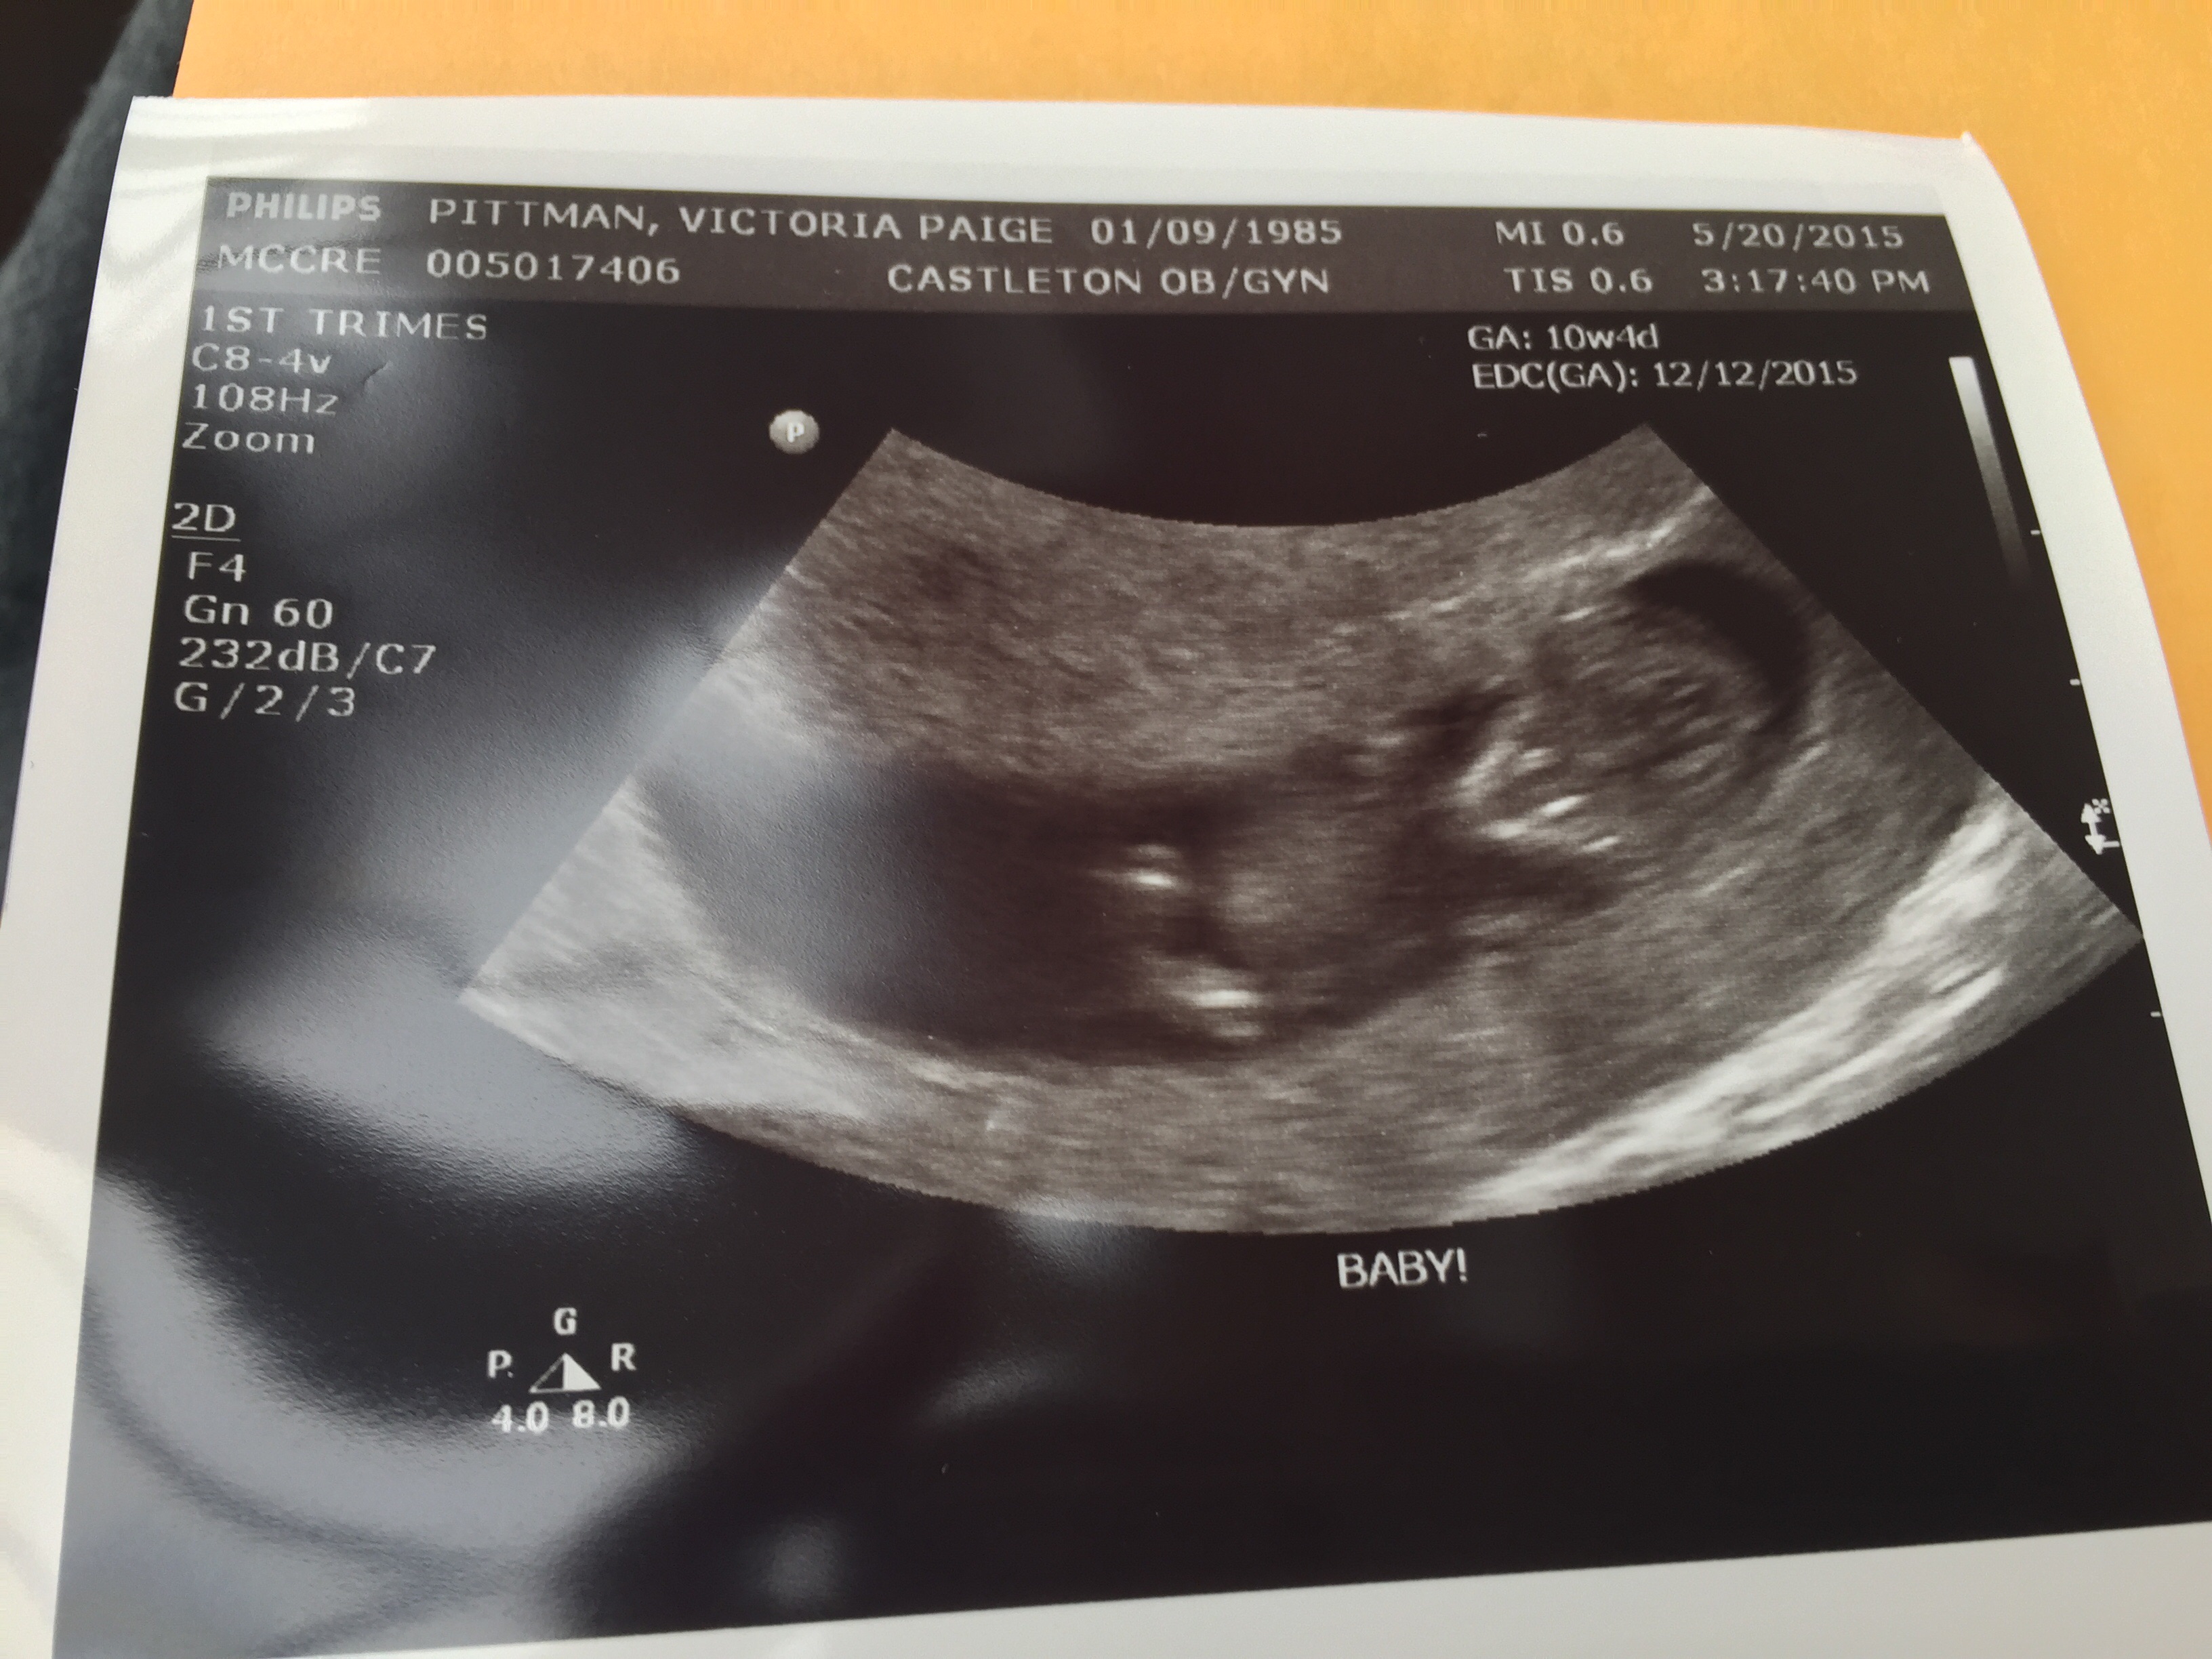

My baby at 11 weeks! Can't wait to have my 12 week scan on Tuesday